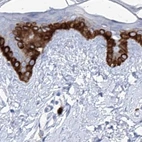

Immunohistochemical staining of human kidney, liver, lymph node and skin using Anti-FRS3 antibody HPA030174 (A) shows similar protein distribution across tissues to independent antibody HPA030162 (B).